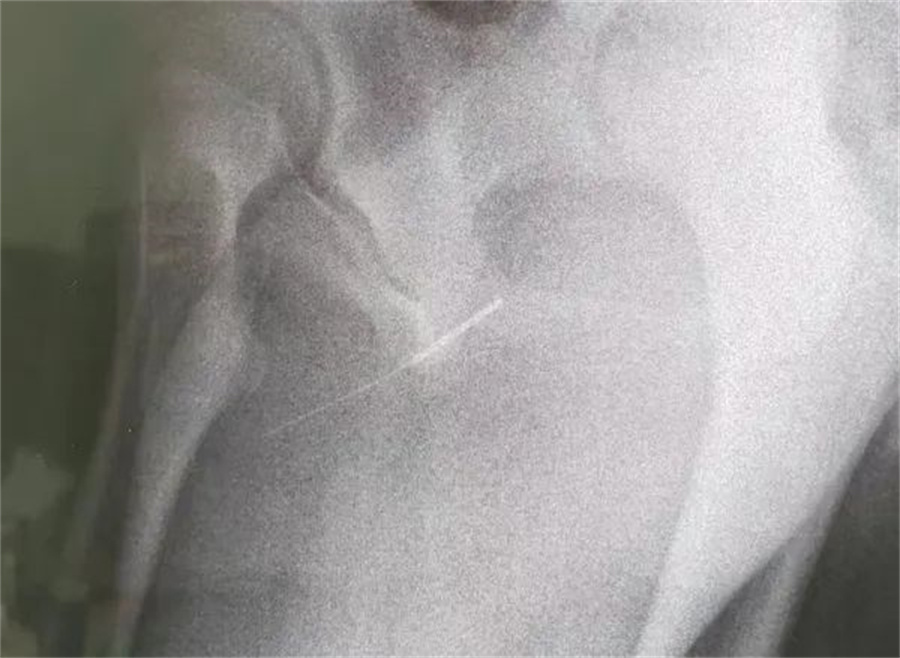

“孩子大概是中午的时候把银针塞进尿道中,因为针灸银针前段柔软纤细而末段又有增粗的螺旋状柄头,所以很难取出来。家长已经带他在当地医院拍片确诊,晚上7点多转到我们医院,当时孩子尿道口有血,疼痛难忍......”德州扑克游戏网

急诊外科接诊后立即收入院并第一时间做好手术准备,此时泌尿外科主任谢方达也紧急从家中赶到了医院,经过术前检查,确认银针卡在了接近球部尿道的部位,位置比较深,又没进入到膀胱里,如何尽快地取针成为一个颇具难度的挑战。

孩子家长和泌尿外科专家都希望用最微创的方式完成手术。但因孩子年龄小、尿道细,体重又偏大而难以实现,术中医生在保证对孩子造成伤害最小的前提下,采取隐匿小切口的方式,顺利将6.5cm的银针从尿道中刺破取出,为孩子解除了困扰,术后恢复三四天后即可顺利出院。